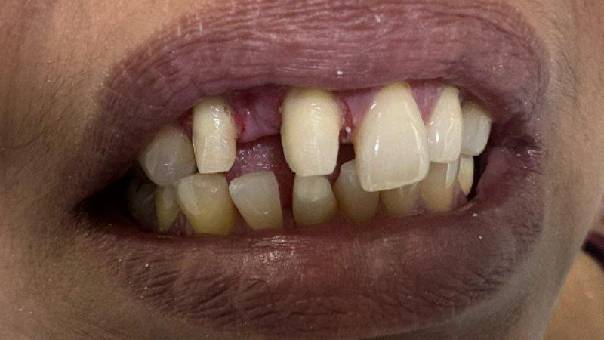

Patient Concern: A middle-aged female patient visited our clinic with a primary concern about spacing in her upper front teeth. She was particularly self-conscious about the gap and was seeking an aesthetic and long-lasting solution.

Pre-operative picture

Diagnosis: Upon clinical and radiographic examination, we discovered the presence of a mesioden—an extra tooth located between her Upper Right Central and Lateral Incisor. This supernumerary tooth was contributing to the spacing and misalignment in the anterior region.